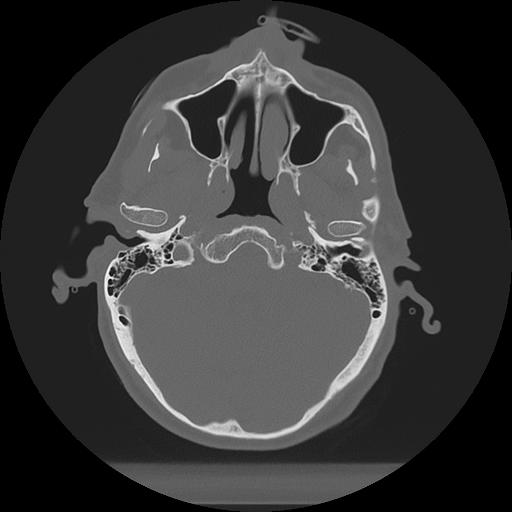

11 HUESO,,Axial,2.0,HUESO,,